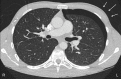

A 19-year-old male patient was referred by his general practitioner with a new 'cardiac murmur'. For 1 week, he had been able to provoke a clicking sound, which was in time with his heart beat and originated from his chest. The physical examination and laboratory tests were normal. The sound was initially interpreted as most likely due to a valve condition such as mitral valve prolapse, but a transthoracic echocardiogram was normal. A cardiac CT was obtained, which showed left-sided ventral pneumothorax.The Hamman's sign is a loud precordial pulse synchronous sound, which is often postural. It is pathognomonic for left-sided pneumothorax or pneumomediastinum. Hamman's sign as a presenting symptom is rare, but if present is key to diagnosis. The awareness of rare clinical findings is important and will prevent unnecessary diagnostic tests.